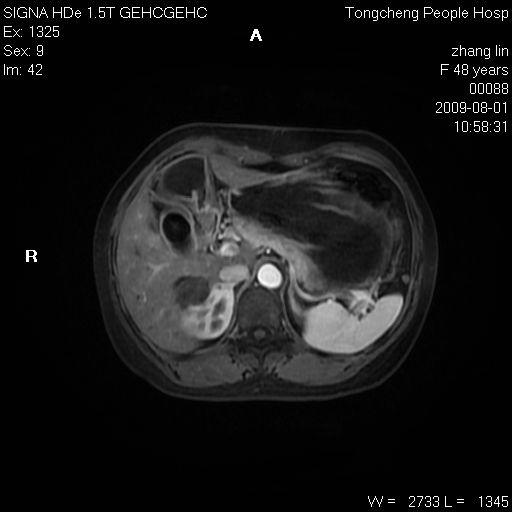

女,48岁。健康体检,彩超发现右肾占位性病变。平素健康。

临床诊断:右肾占位性病变,性质待定(囊肿?肿瘤?)。

上中腹部mr平扫+增强扫描,图像如下:

右肾上极见一类圆形病灶,t1wi呈等信号t2wi呈等高混杂信号,三期增强无强化,边界清---考虑囊肿出血。

肝囊肿

慢性胆囊炎